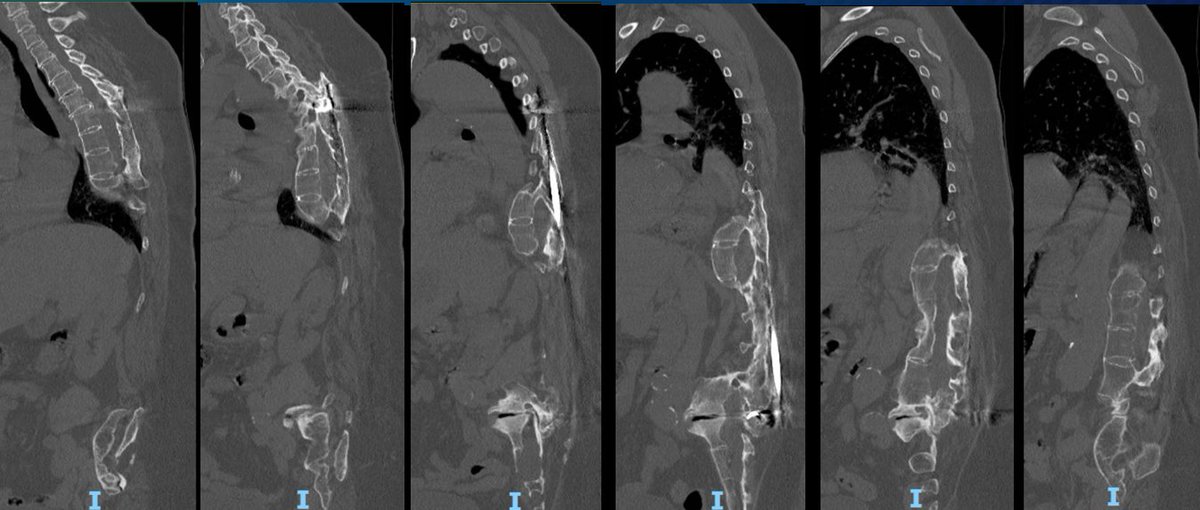

50s patient with severe malalignment. How would you treat this surgically? Nnee compensation in coronal and sagittal planes. Options: Multisegment instrumentation, TLIF/ALIF/OLIF, PSO, refer to another surgeon? Thoughts? #neurosurgery #spine #scoliosis #flatback #harringtonrods

Severe malalignment case: Performed T12-S1/Pelvis posterior instrumentation, TLIF at L5-S1 & L5 PSO. No anterior approach on vascular team's advice. Patient now stands upright & grateful. #SpineSurgery #MedTwitter #scoliosis #flatback #HarringtonRods #ScoliosisWarrior